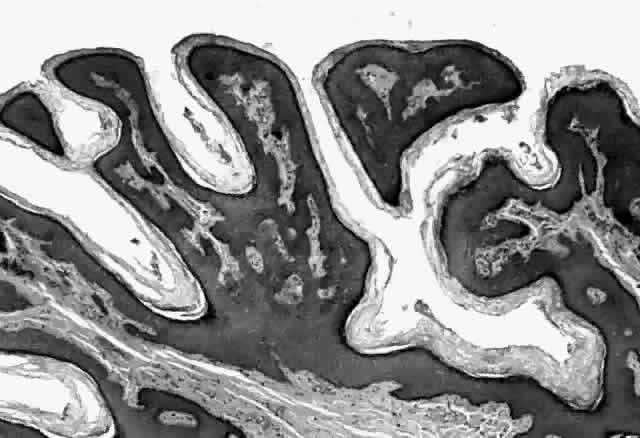

HPV-induced conjunctival squamous papillomas demonstrate papillomatosis, acanthosis, and koilocytosis (Fig. 6). Because they are mucous membrane lesions, those of the conjunctiva and lacrimal sac show no granular cell layer but will show keratinization if they are large or exposed (Fig. 7). In our experience the frequency of koilocytes is variable, even in lesions almost certain to be viral (Fig. 8). Scattered inflammatory cells may be present in the cores or epithelium. Virus can be detected immunohistochemically in the nuclei of the cells (Fig. 9).

Squamous papillomas of the eyelid are exophytic lesions with multiple fronds, each showing acanthotic epithelium around a fibrovascular core. There is typically hyperkeratosis and koilocytosis. Inflammatory cells may be present.